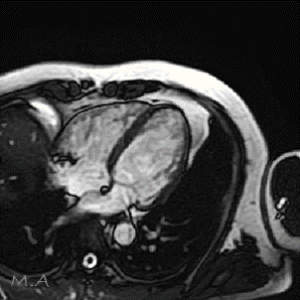

MRI

MRIとはMagnetic Resonance Imaging(磁気共鳴画像法)の略で、強力な磁石と電波を使って様々な角度から体の断面を画像化する検査です。

X線を使用しないため、放射線被ばくの心配がなく、軟部組織(筋肉、靱帯、神経など)の描出に優れており、がんの有無や広がり、転移の有無などを調べることができます。また、造影剤を用いずに血管を描出することが可能です。

部位や目的により異なりますが、検査時間は15分から40分程度です。複雑で高度な検査の場合は60分程かかる場合もあります。

当院ではCanon社製Vantage Fortian MRI 1.5Tを設置しており、主に脳血管疾患、脊椎疾患、閉塞性動脈硬化症などの下肢疾患、腹部疾患、心臓疾患、関節等の検査を行っています。